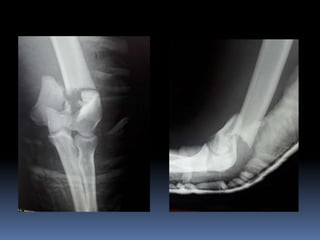

Este documento trata sobre las fracturas del tercio distal del húmero. Brevemente describe que representan el 0-5% de todas las fracturas, que la mayoría son del tipo C, y que pueden causar lesiones de tejidos blandos y nervios. Explica que en niños la línea de fractura suele ser supracondilea. Además, cubre temas como la anatomía relevante, mecanismos de lesión, clínica, diagnóstico, clasificación, y tratamiento quirúrgico y conservador de estas fracturas.